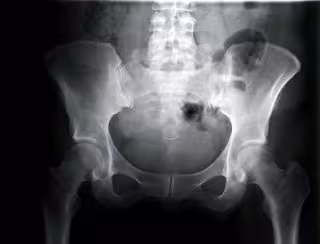

Cadera de mujer vista con rayos.

GETTY